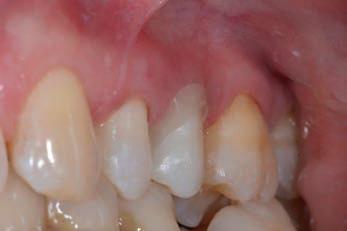

After 4 more weeks, the prosthetic abutment was refined and the definitive dental impression was taken with poly vinylsiloxane-ether (PVS-E, Exa’Lence™, GC) (Figs. 13-14). The dental impression was sent to the laboratory, where it was optically scanned and a CAD-CAM path was set.

Figure 13: Final preparation of the tooth with the aim of taking the definitive impression. Note the total absence of bleeding despite having extended the preparation margins more apically than the first provisional. Figure 14: Definitive impression in PVS-E. The impression was scanned by a laboratory scanner and an entire CAD-CAM path was created for milling the final crown.